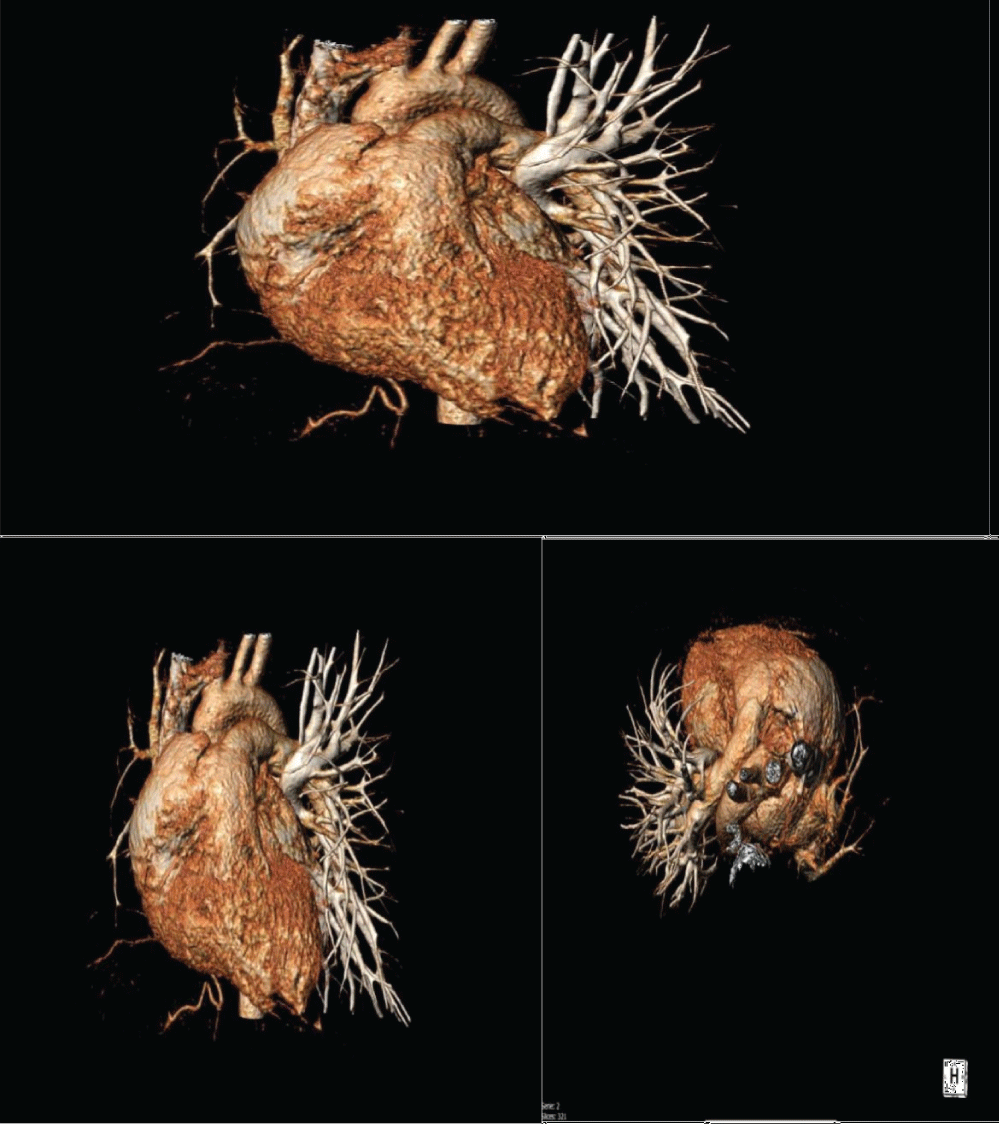

Figure 2: Case 1 CT scan 3D reconstruction showing right pulmonary artery agenesis. View Figure 2

A 21-year-old woman presented for a history of exertional dyspnoea and atypical chest pain. No history of allergies or tuberculosis. A chest X-ray showed asymmetry of the chest walls from a reduced expansion of the right lung caused by parenchymal loss and right deviation of the mediastinum and ipsilateral elevation of the diaphragm. Transthoracic echocardiogram showed high value of estimated systolic pulmonary pressure (sPAP 45 mmHg) with normal right ventricle (Figure 1A). Right pulmonary artery not viewable. Pulmonary scintigraphy releaved low ventilation with no perfusion of the right lung, with a normal left lung (Figure 1B). Spirometric test showed a restrictive-like dysfunctional pattern with mild reduction of DLCO, 6MWT: reduction in distance walked without desaturation. CPET: normal exercise tolerance with augmented heart rate response, VO2/HR 9.7 mL/beat; VE/VCO2 45; VO2max 31 ml/kg/min, compatible with pulmonary hypertension. Angio-CT scans of the chest showed right PAA with hypertrophic ipsilateral diaphragmatic and bronchial arteries; right lung hypoplasia with diffuse bronchiectasis area (Figure 2). A right heart catheterization confirmed a borderline precapillary pulmonary hypertension without vaso reactivity and right PAA (BOPAH; sPAP 40 mmHg, mPAP 22 mmHg, PVR 1.8 UW) (Figure 3). No specific therapy for PAH was started.